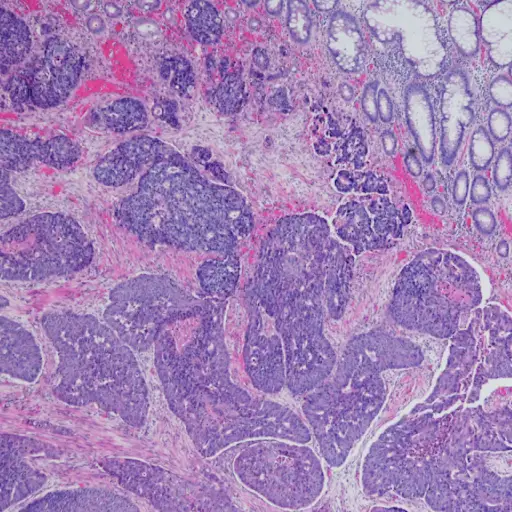

结直肠癌筛查的金标是一个结肠镜检查在这种手术中,一根管子插入结肠以寻找息肉,过度生长上皮组织那条线肠。大多数息肉是无害的,但它们可以变成称为恶性肿瘤腺癌。如果你的医生看到有问题的地方,她会活检- 将组织样本 - Samir Gupta,M.D.是加州大学圣地亚哥健康的胃肠学家。样品进入实验室组织学,在显微镜下的组织研究以寻找癌症。